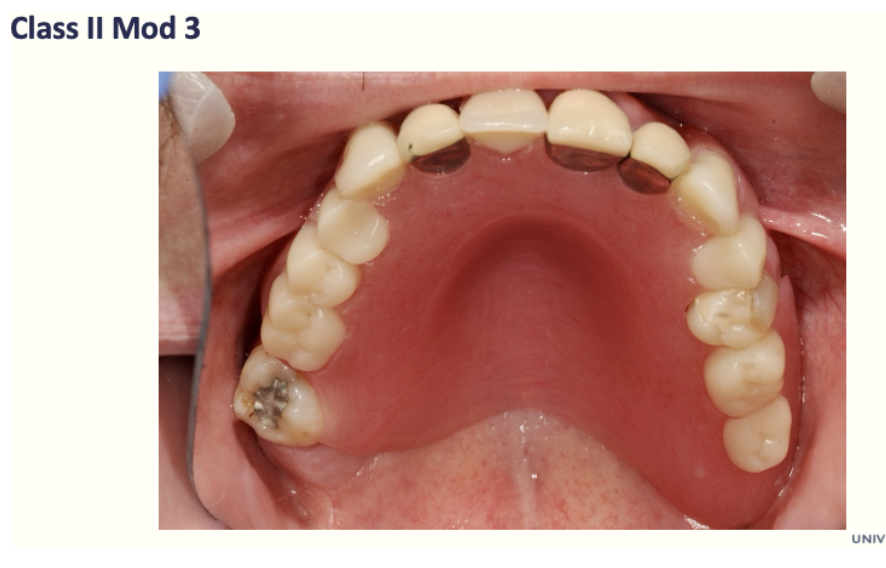

21

Q

What is Class II Mod 3

A

Class 2

Free end saddle at LHS

3 other saddles replacing UL4 ,UR1

And saddles replacing upper L 3,4,5,6

How well did you know this?